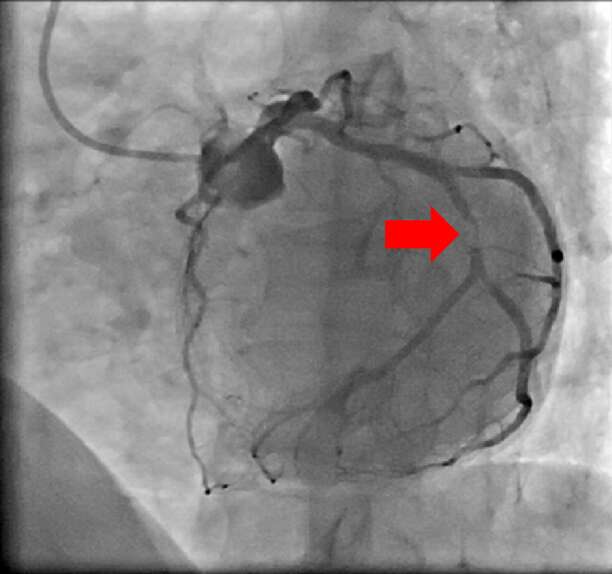

【治療例3:狭心症ステント拡張術】

心臓に栄養を送る血管を冠動脈と呼びますが、冠動脈が狭窄すると心筋梗塞や狭心症を発症します。

冠動脈の狭窄又は閉塞を専用の治療器具を用いて治療していきます。

治療前

赤矢印の冠動脈が狭窄している

治療後

狭窄していた冠動脈にステントを留置し、血流が元に戻っている